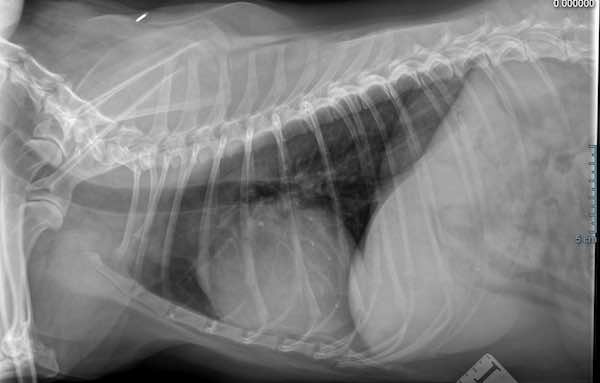

🩻 Chest X-rays: To check the size of the heart and assess lung health.

On a chest radiograph (or X-ray) the heart appears in silhouette only.